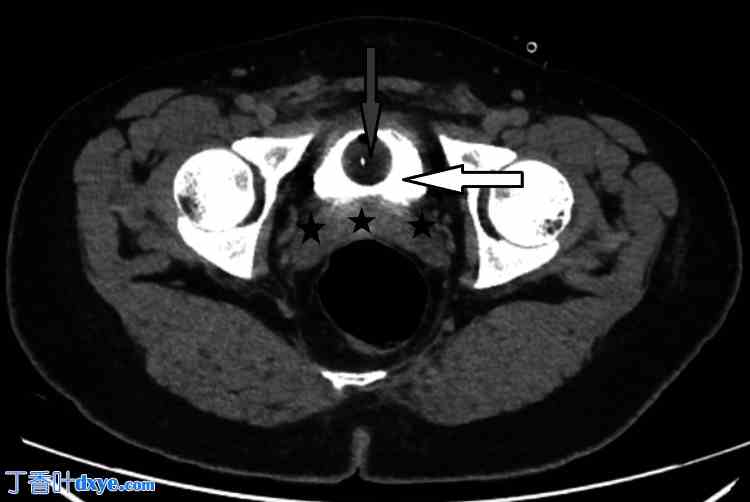

术后,患者恢复良好,仅下腹部不适。术后第1天(POD 1),血液检查结果显示白细胞计数(WCC)为13.11 x 10³/μL(参考值2.2-10),C反应蛋白(CRP)为69.23 mg/L(参考值0-5)。引流液仅为15 ml,呈浆液血性。然而,术后第2天(POD 2),引流量增至55 ml,术后第3天(POD 3)增至220 ml。此时,怀疑存在漏诊的膀胱损伤,引流液分析证实了这一诊断,引流液肌酐水平为11354 μmol/L(参考值3450-22900),而患者血清肌酐水平为69 μmol/L(参考值45-100)。插入Foley™导尿管(Microtech,德国门兴格拉德巴赫),并安排进行腹盆部CT扫描。CT延迟期显示输尿管或膀胱无明显造影剂渗漏,盆腔内仅有少量游离液体(如图1-2所示)。CT结果支持轻微膀胱损伤已自行愈合的诊断,因为插入Foley导尿管后未见渗漏,这支持了作者对该患者采取保守治疗方案。

图1. 术后第3天腹部CT轴位图像(10分钟延迟期),显示膀胱内有造影剂(白色箭头),膀胱周围区域无造影剂渗漏(黑色星号),Foley导尿管(灰色箭头)位置良好。

白色箭头:膀胱内有造影剂,灰色箭头:导尿管,黑色星号:膀胱周围区域无造影剂渗漏